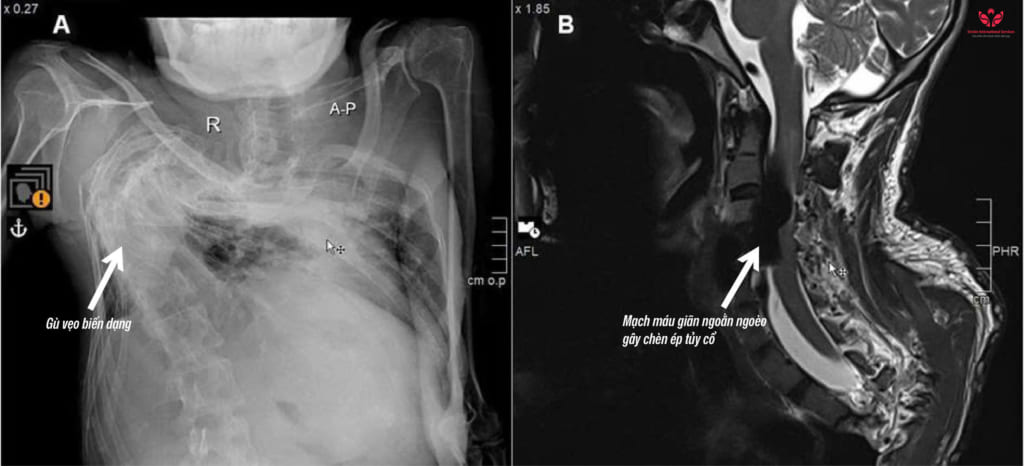

Qua thăm khám và chụp MRI, bác sĩ phát hiện anh N. bị bệnh rò động tĩnh mạch vùng cột sống làm cho tĩnh mạch quanh tủy sống vùng cổ giãn ngoằn ngoèo, tạo thành một khối lớn gây chèn ép. Tình trạng này là nguyên nhân khiến anh N. bị yếu liệt tay chân, đau nhức và khó vận động. Bác sĩ nhận định, đây là một bệnh lý cực kỳ hiếm gặp.

Trường hợp này phức tạp hơn nhiều so với thông thường vì cột sống biến dạng nặng, giải phẫu mạch máu bị thay đổi theo, khiến việc tiếp cận điều trị trở nên rất khó khăn.